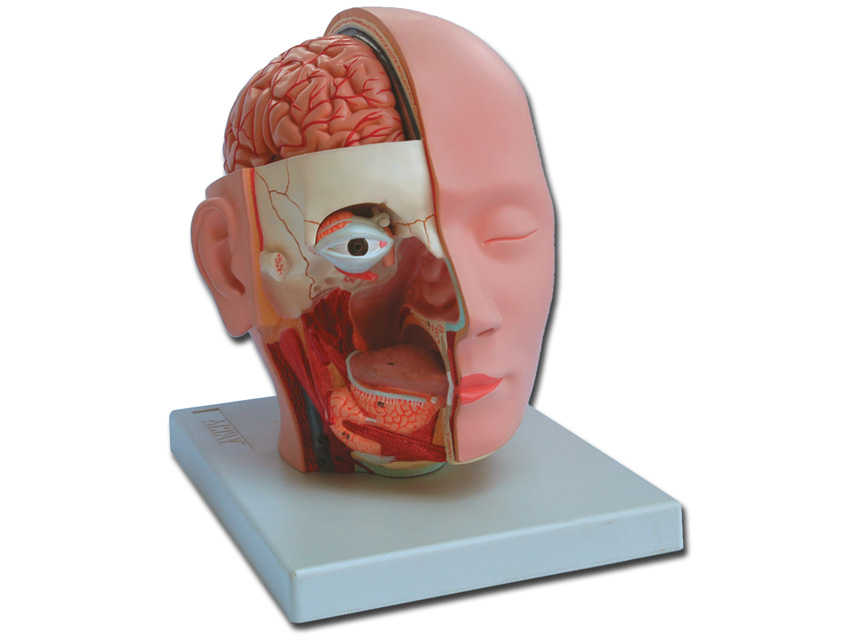

MODELLO TESTA - 4 parti - 1X

Modellino anatomico di dimensioni reali composto da 4 parti, come segue:

- Metà cervello, mostra la struttura interna del cerebrum e i relativi vasi sanguigni

- Metà cerebellum

- Occhio con nervo ottico

Il lato destro della faccia è sezionato lungo la linea orizzontale e sagittale. Questo modellino anatomico molti dettagli significativi del cervello a del cranio assieme all'intera cavità oro-nasale. • Dimensioni: 18 x 25 x h 23 cm

• Parti: 4

• Ingrandimento: 1X